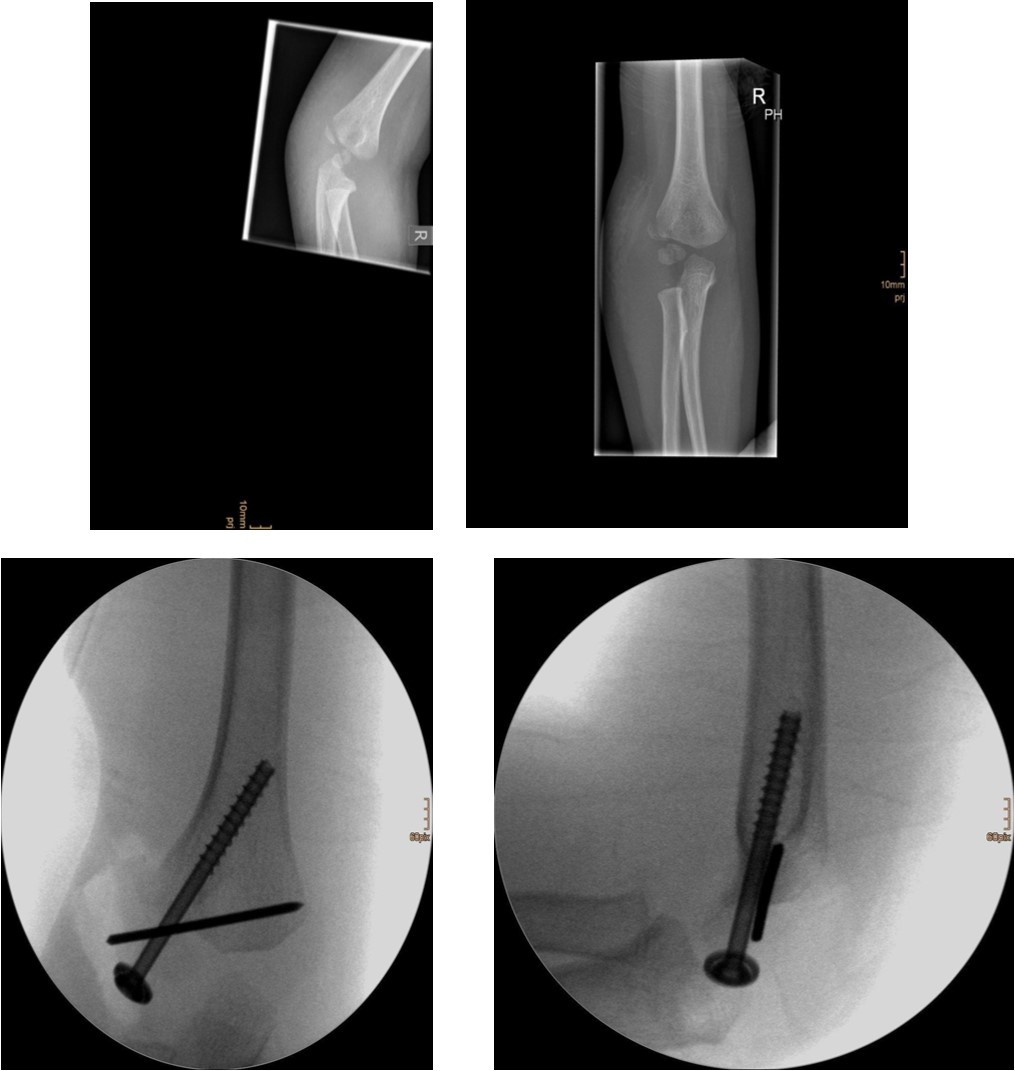

The degree of displacement may be seen on the true lateral view. In determining whether the articular hinge is intact (i.e., stage I vs. stage II), the relationship of the proximal ulna to the distal humerus is evaluated for the presence of lateral translocation. Oblique views are especially helpful in patients in whom a stage I displacement is suspected but not evident on AP and lateral views. Figure 1 and Figure 2.

Figure 2.6 year old male patient with a dislocated right lateral condyle fracture which was treated by open reduction and osteosynthesis with a screw and a Kirschner wire (personal collection)

Non-displaced and stable fractures may be treated by cast immobilization with close follow-up, but fractures displaced >2 to 3 mm may indicate surgical fixation 7, 8. Surgical treatment can be done either by closed reduction and percutaneous osteosynthesis or open reduction and osteosynthesis. Figure 3.

Figure 3.9 year old male patient with a elbow dislocation and a dislocated left lateral condyle fracture which was treated by open reduction and osteosynthesis with a screw (personal collection)

Surgical fixation is either by screw, smooth K-wires or both. The K-wires can be buried under the skin or not.